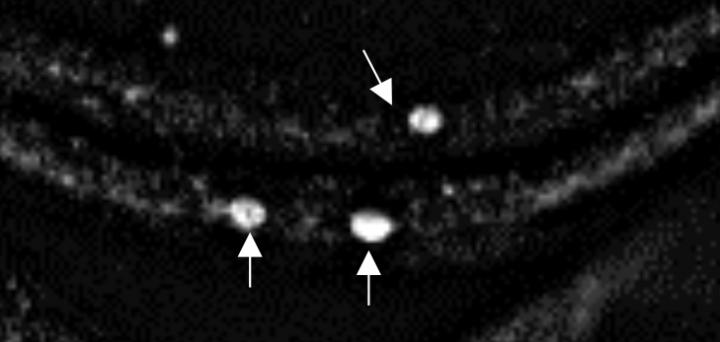

BUFFALO, N.Y. -- Research by University at Buffalo biologists is providing new insights into alpha-synuclein, a small acidic protein associated with Parkinson's disease.

Alpha-synuclein is known to form abnormal clumps in the brains of patients with Parkinson's, but scientists are still trying to understand how and why this happens.

The new study explores alpha-synuclein's basic properties, with a focus on a section of the protein known as the non-amyloidal component (NAC). The research was done on fruit fly larvae that were genetically engineered to produce both normal and mutated forms of human alpha-synuclein.

"We show that in fruit fly larvae, we're able to prevent some problems mimicking symptoms of Parkinson's disease, such as accumulation of alpha-synuclein in neurons," says Gunawardena, PhD, associate professor of biological sciences in the UB College of Arts and Sciences.

"Our work highlights a potential early treatment strategy for Parkinson's disease that would leverage the use of deletion of the NAC region," Gunawardena adds. "One reason this study is important is because it shows rescue of alpha-synuclein aggregates, synaptic morphological defects and locomotion defects seen in Parkinson's disease in the context of a whole organism."